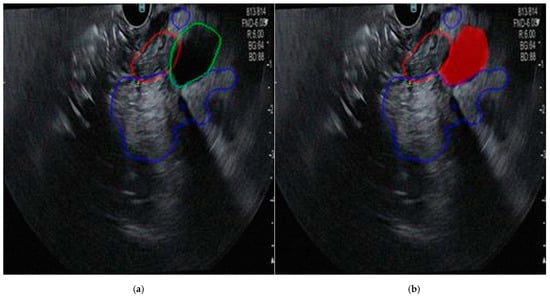

Given the limited size of the dataset, image augmentation was necessary to increase its diversity and ensure the model could handle the variability of real-life images. Augmentation techniques applied included random rotations between −30 and +30 degrees, horizontal mirroring, random translations on the X and Y axes up to +/− 10 pixels, random scaling between 0.9 and 1.1 times the original size, and adding Gaussian noise with mean 0 and variance 0.01. Each original image was augmented to create approximately eight additional copies, each with one of these techniques applied randomly. This process resulted in 848 images containing tumors and 400 images with a healthy pancreas. To ensure compatibility with the model’s input requirements, all images and corresponding labels were resized to 256 × 256 pixels. This uniform resizing enabled the training of the convolutional neural network (CNN), prevented errors due to varying image sizes, and ensured consistency across the dataset. Training the CNN for detection and segmentation required both the original images and binary masks corresponding to the labeled organs. These masks, created from the labeled images, denoted the tumor, pancreas, and bile duct regions. An example of an image and its corresponding mask is presented in Figure 1.

Figure 1. (a) EUS aspect of a dCCA; (b) binary mask for tumor.